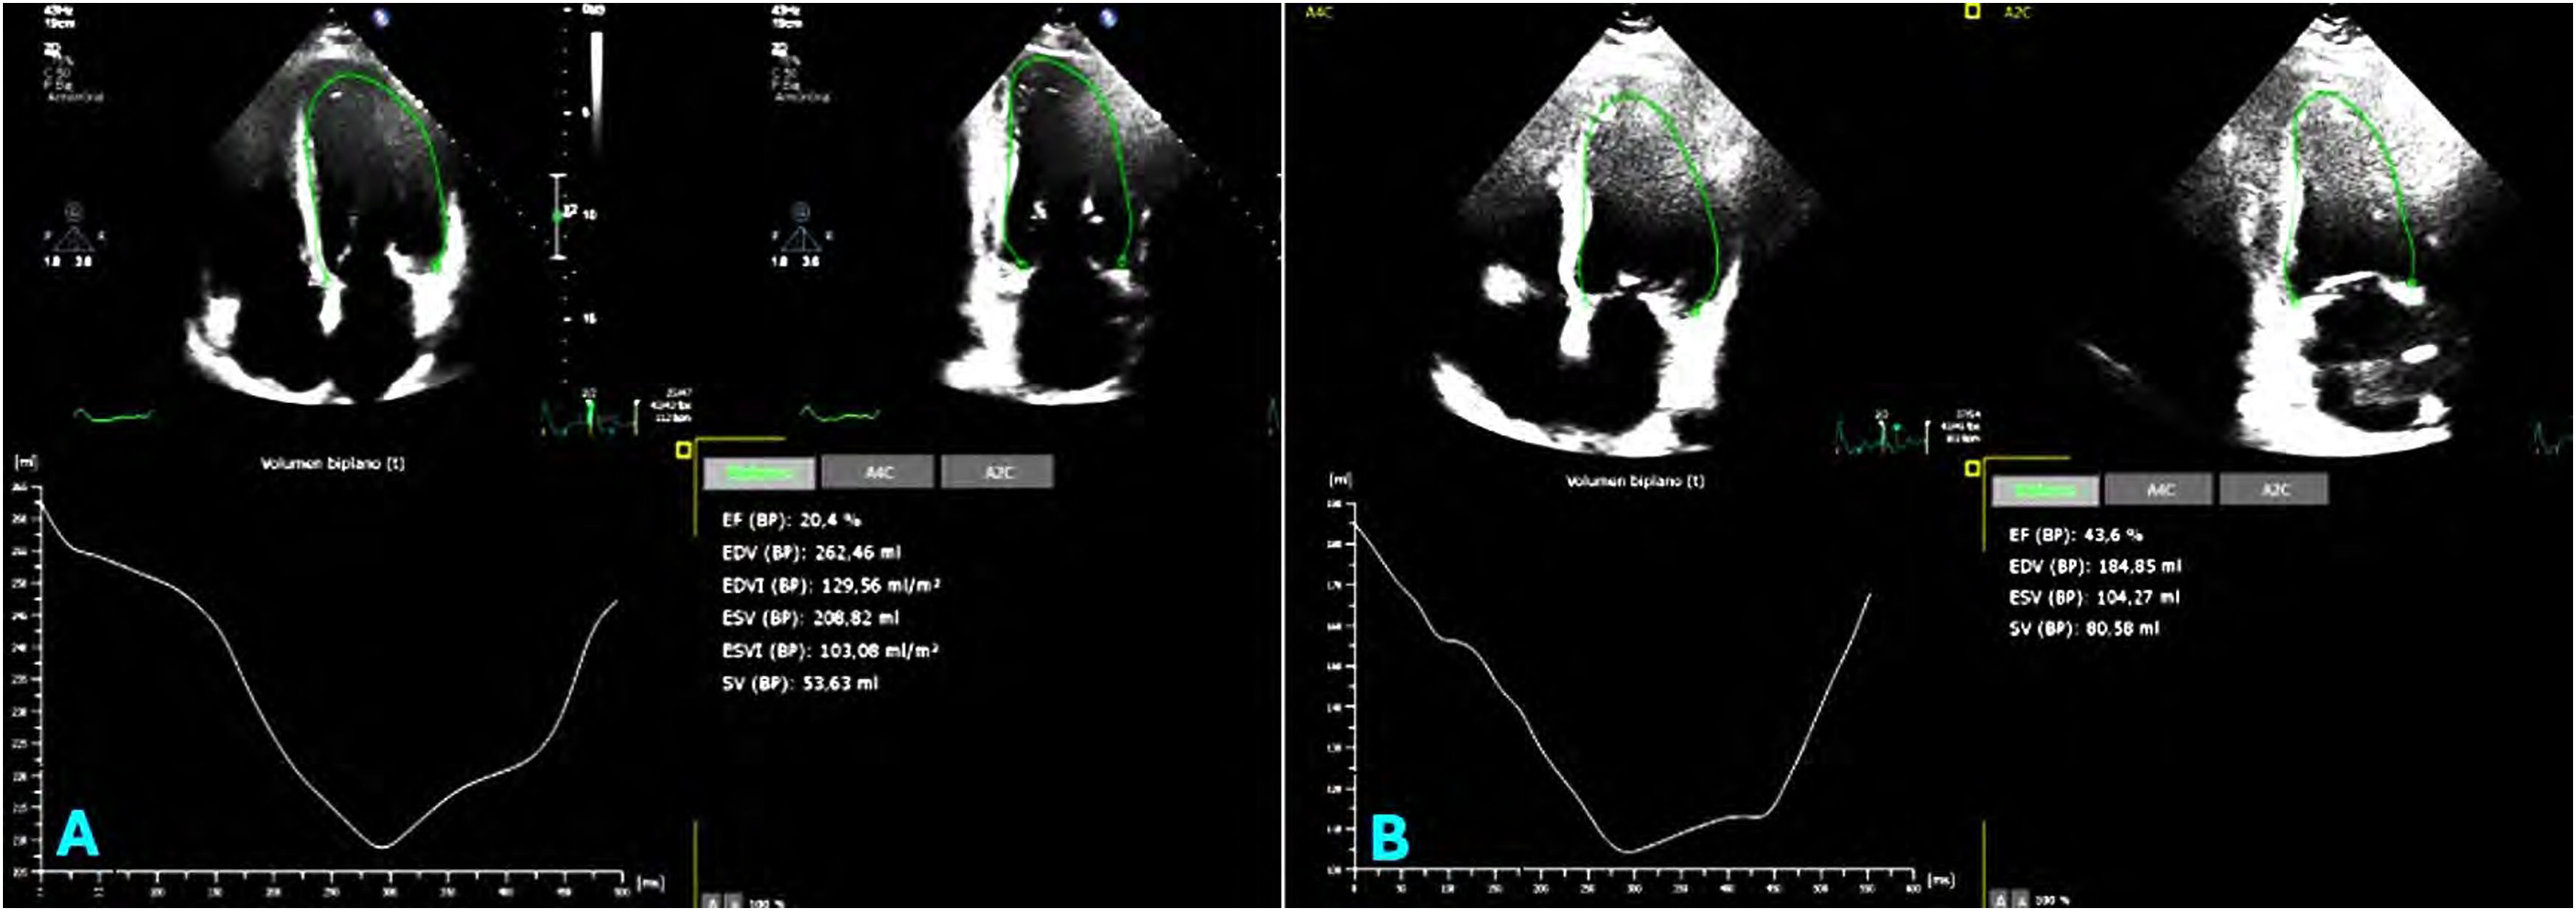

Iron heart: cardiomyopathy secondary to liver disease

Corazón de hierro: miocardiopatía secundaria a hepatopatía